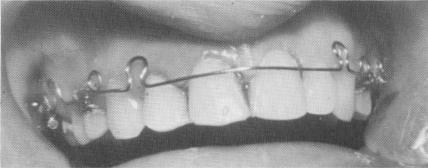

Fig. 13-23. As a result of an accident to a 16-year-old girl undergoing orthodontic treatment, her right lateral incisor was so loose that it came out of the socket with an alginate impression.

Fig. 13-24. The right lateral incisor and both central incisors were prepared for full crown restorations. The canal of the tooth was then treated and the tooth reimplanted with a stabilizer.

Accidental injury to a 16-year-old girl undergoing orthodontic treatment necessitated reimplantation (Fig. 13-23). As a result of a fall, the girl's lateral incisor was so loose that it came out of her mouth when an alginate impression was taken for fabricating a removable splint. With the tooth out-side the mouth, the nerve was removed, the canal widened, and an implant pin placed through it to ensure proper fit. The endodontic stabilizer was re-moved from the tooth and the tooth was placed back into the socket. While holding the tooth firmly in place, a long endodontic spiral drill was placed in-side the hollow root canal, and, with a slow-running contra-angle drill, a hole was made into the bone above the canal and as deep as possible without involving the floor of the nasal cavity. The drill was then removed and, with the use of Kri paste and oxyphosphate of zinc cement, the endodontic stabilizer was placed back in the tooth (Fig. 13-24). The pin was tapped deep into the bone to stabilize the tooth, and crowns were cemented over the reimplanted tooth and its abutments (Fig. 13-25). Fig. 13-26 is an x-ray of the finished case.